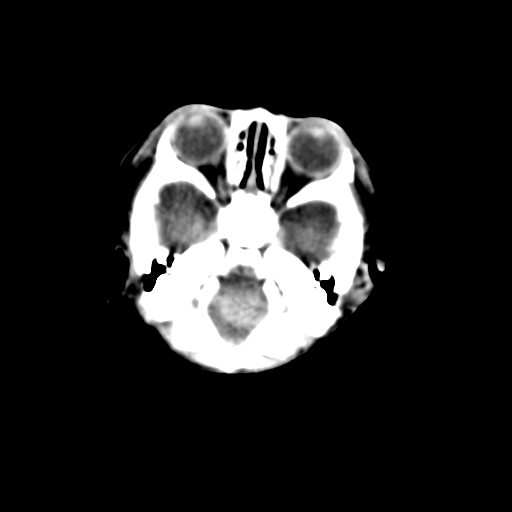

新生儿女2天,有窒息史,经抢救好转!白质最低ct值>23hu,请教各位老师:是否有出血?是否合并缺氧脑病?谢谢!

hie、蛛网膜下腔出血,皮下血舯。

空三角征,蛛网膜下腔出血。